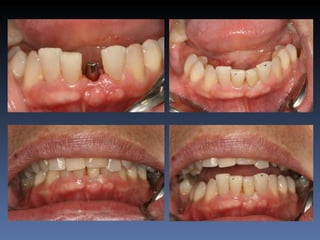

BOX 4

Ville Victorazzo Carmo

Idade – 20 anos

Sexo – Masculino

Raça – Caucasiana

ASA – I

Data- 27-04-2012

Diagnóstico: Desdentado da zona 2.1,

pré-regenerada.

Plano de tratamento: Instalação de implante endo-

ósseos ( 2.1 ) para reabilitação protética fixa.